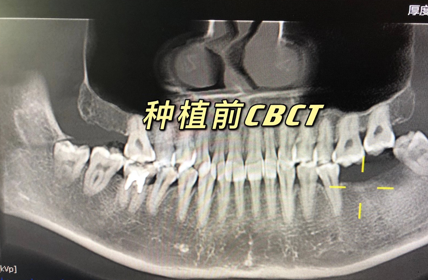

翟强种牙案例,夫妻俩特意从下沙过来找翟主任种植哦~今天先种两颗,下次再来种另一边的~感谢对坚果满满的信任。